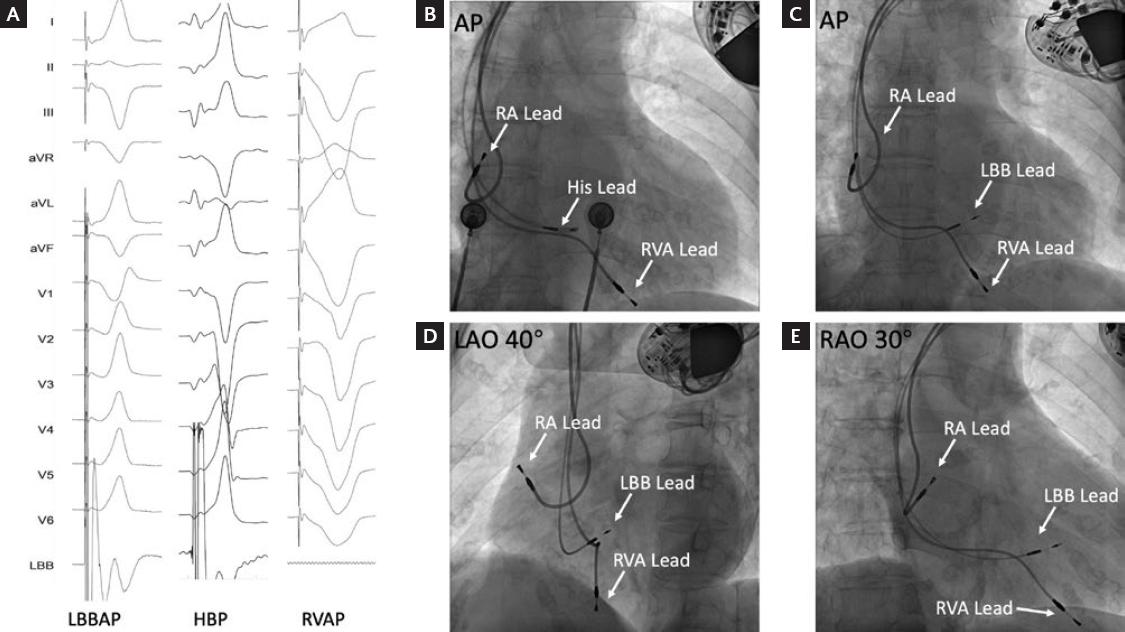

Figure 4 shows that in this study, a patient with a dual chamber pacemaker who previously underwent right ventricular apical pacing (RVAP) was treated by pacemaker replacement using LBBAP due to battery depletion. The original ventricular electrode was abandoned in the right ventricle without being pulled out. As shown in the figure, LBBAP, HBP, and RVAP were quite different in pacing ECG and fluoroscopic images. In the pacing ECG, LBBAP shows as an incomplete RBBD with narrow QRS, HBP as an approximately normal ECG, while RVAP as a complete left bundle branch block with wide QRS.

Figure 4 Comparison of pacing electrocardiogram and fluoroscopic image between LBBAP, HBP, and RVAP. A, comparison of pacing electrocardiogram (3.5 V at 0.5 ms) between LBBAP, HBP, and RVAP. B, fluoroscopic image of 3830 lead in His position. C-E, final fluoroscopic image in three projections (AP, LAO40°, and RAO30°) of a patient treated by pacemaker replacement from RVAP to LBBAP. LBBAP: left bundle branch area pacing; HBP: His bundle pacing; RVAP: right ventricular apical pacing; RVA: right ventricular apex; LBB: left bundle branch; RA: right atrium.